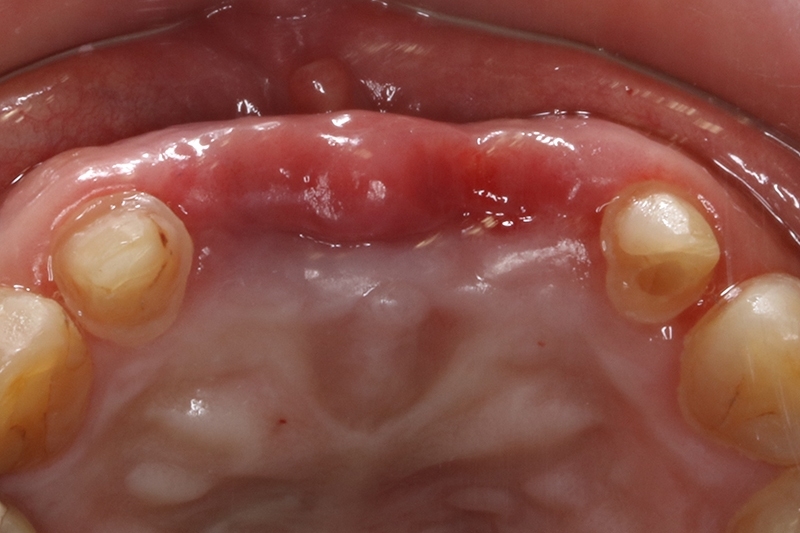

牙周治療前病患抱怨有膿在舊有的門牙植牙周邊,容易流血

經過牙周治療後,控制發炎,可見牙齦的狀況變得更健康了!

接續牙周治療完成後的療程,上排門牙植牙的問題處理,長期不斷的發炎化膿流血,除了造成周圍組織發炎與牙齦腫脹,同時造成齒槽骨被細菌破壞與吸收,根本解決的方式是建議移除感染與位置不佳的植體,先進行植牙移除手術+齒槽骨保存術,先使用膠原蛋白促進軟組織癒合,加快癒合的速度。